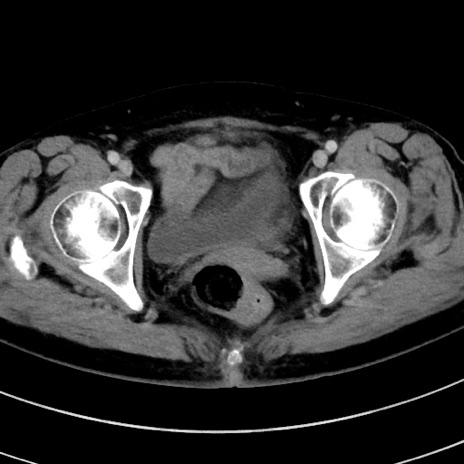

症例9(横断像)

【症例】 60歳代女性

【主訴】むかつき、みぞおちの痛み

【現病歴】3日前よりむかつきがあり、食事がとれない。

【既往歴】糖尿病

【身体所見】発熱なし、心窩部圧痛軽度あるも、腹膜刺激症状なし。

【データ】WBC 7400、CRP 1.92